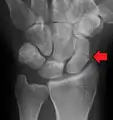

A more obvious scaphoid fracture on a scaphoid view X ray

Radiolucency around a 12 days old scaphoid fracture that was initially barely visible.[13]